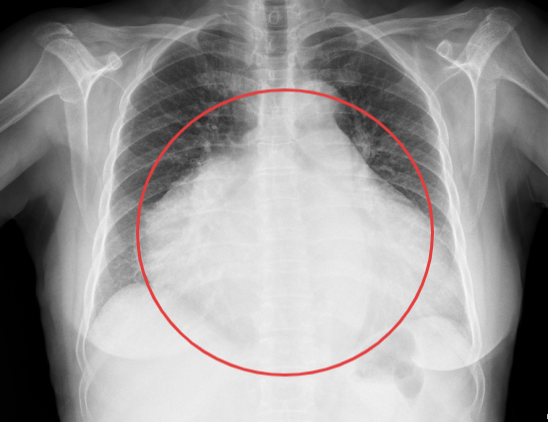

患者楊阿姨,因右下腹脹痛持續一月入院,經過詳細的腹部CT檢查,結果顯示其腹腔內存在一個巨大占位性病變,最大層面大小竟達到了驚人的18cm×10cm×14cm,腫瘤性質及來源尚不明確。面對如此龐大的腫瘤,手術難度可想而知。然而,楊阿姨的身體狀況更為復雜。術前檢查發現,她全心擴大,心臟彩超顯示三尖瓣大量反流,肺動脈高壓、二尖瓣大量反流,肺動脈瓣中量反流,并伴有心動過緩。這些心臟問題無疑為手術增添了巨大的風險。面對這樣心功能極差的患者,任何微小的失誤都可能導致不可挽回的后果。